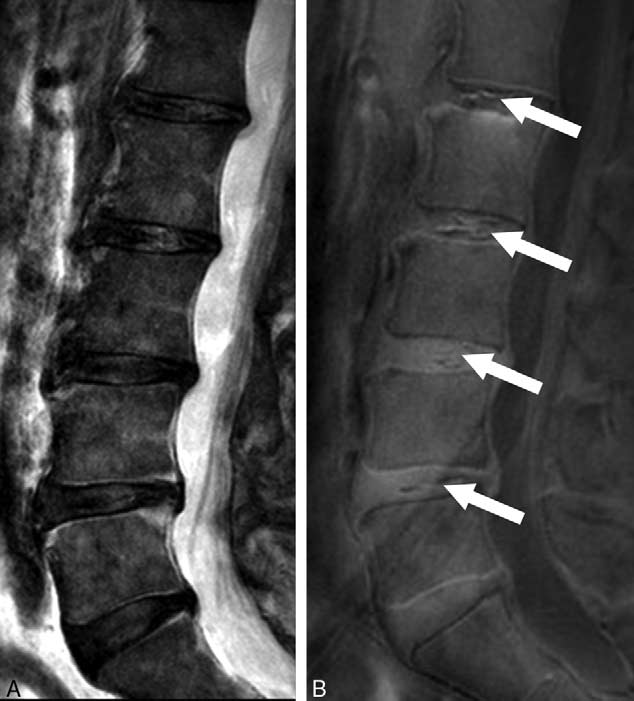

近年世界各地的研究人員都致力研發各種新款的磁力共振技術,希望能為腰椎退化及腰背痛的診斷邁進一步。當中一項嶄新的影像技術為超短時間回波磁力共振(UTE MRI),它能分析人體中含有短回波的軟組織,而這亦是傳統MRI所不能檢測及分析到的。港大的研究團隊利用了UTE MRI技術,首次於人體發現一種名為UTE 椎間盤病徵(UTE Disc Sign / UDS)的嶄新影像指標,在腰椎退化及腰背痛的臨床診斷上帶來重大的啟示。UTE MRI可在現有的MRI儀器上進行,只需約15-20分鐘便能完成掃瞄,與傳統的MRI所需時間相約。

這次研究共有108名華南地區人士(平均年齡52歲,男女各半)參與。傳統的T2W MRI用作評估椎間盤退化和其他影像病徵,T1-rho MRI用作量度構成椎間盤的主要成份 “蛋白聚醣”水平。UDS 病徵被定義為在UTE MRI上檢測到的超高或超低光束帶。參與者的基本資料、病歷、腰背痛情況及活動能力指標(ODI Oswestry Disability Index)亦於研究時採納為臨床指標之一。

研究結果發現39.8%的參與者有UDS病徵,而其中61.4%的UDS是發生於下腰部位置。有UDS病徵比沒有UDS病徵的參與者有更多機會患有椎間盤退化、椎間盤突出、脊椎移位及椎體變異(Modic Change)。有UDS病徵的椎間盤的蛋白聚醣含量比沒有UDS的椎間盤低。而逾六成UDS病徵是無法在傳統的T2W MRI上檢測到。有UDS病徵的參與者比沒有的參與者有更嚴重的腰背痛,而同時其活動能力亦較差,而傳統的T2W MRI並無法找出此關連。研究更指出約四成患者於多節腰椎皆出現UDS病徵,其患上嚴重腰背痛的機率比單節腰椎出現UDS的患者更高。